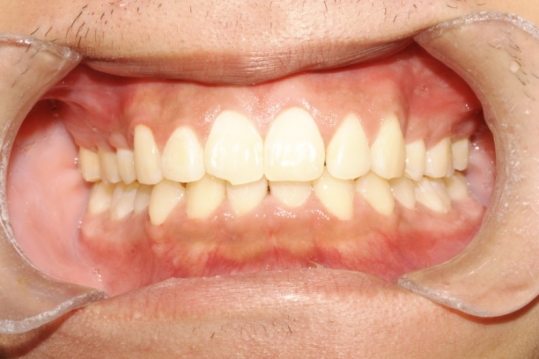

治疗后

治疗前后对比